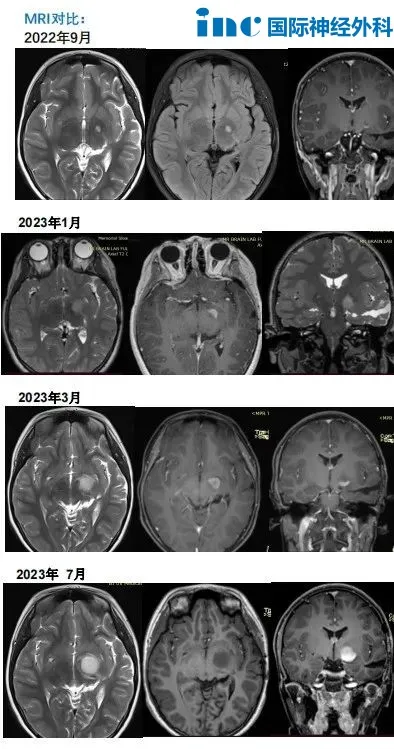

术后MRI对比

2022年,复查MRI发现左侧丘脑微小异常信号,手术医生建议服用靶向药物或化疗,但当时没有采取任何治疗措施,只是继续通过复查核磁共振进行观察。

2023年,再次复查MRI显示病灶明显增大,于是他们再次咨询了之前的手术医生。医生还是建议服用靶向药物。但是,靶向治疗3个月后复查MRI显示病灶进一步增大和强化。